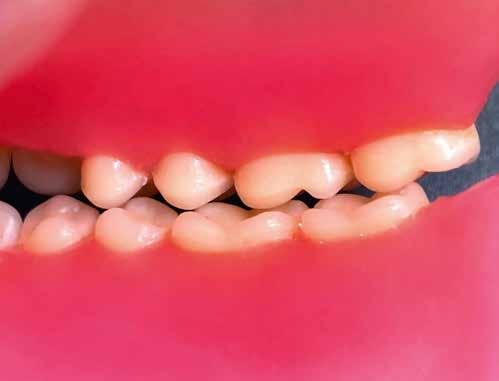

A kiindulási helyzet recessziókkal és szabálytalan éli lefutással.

A pácienseset

Ötvenéves hölgy elégedetlen volt felső frontfogai esztétikai megjelenésével. Ezért elment a rendelőbe. Klinikailag vesztibulárisan két nagy kompozittömés volt megfigyelhető, széli elszíneződéssel. Az élek lefutása egyenetlen, aszimmetrikus volt. A frontfogakon recessziók és a nyakak szabaddá válása volt megfigyelhető. A hölgy a fogív gyors restauratív nivellálását kívánta. A nagymetszők közötti diasztémát csökkenteni kellett, de nem zárni, hogy megmaradhasson az optimális hossz-szélesség arány. A recessziók kötőszöveti fedését műtéttel kizárta. Viaszmintázat és intraorális mock-up segítségével szimuláltuk a teljes kerámiahéjakat, illetve segítettük a minimálinvazív preparációt a zománc területén. A páciens világos színű restaurációt akart. Vázanyagként a felső frontok területén a VITA AMBRIA anyagot terveztük használni, hogy a héjak életteli, színhelyes alapot kapjanak, egyidejűleg elérve az igen magas, 500 MPa-os szilárdságot. Az egyéniesítés megvalósítását VITA LUMEX AC leucit-erősítésű üvegkerámiával terveztük, hogy kevés, szín- és formastabil égetéssel reprodukálhassuk a fogakat. A 23-as szemfogat – palatinálisan megfigyelhető defektusa miatt – egyedüliként teljes koronával terveztük rehabilitálni, ugyanezzel az anyagkombinációval. A bukkális folyosó feltöltése érdekében a premolárisokra is héjak kerültek. Ezek természetes fluoreszcenciájának, transzlucenciájának és opaleszcenciájának eléréséhez monolit VITA AMBRIA munkákat készítettünk, felszíni festéssel.